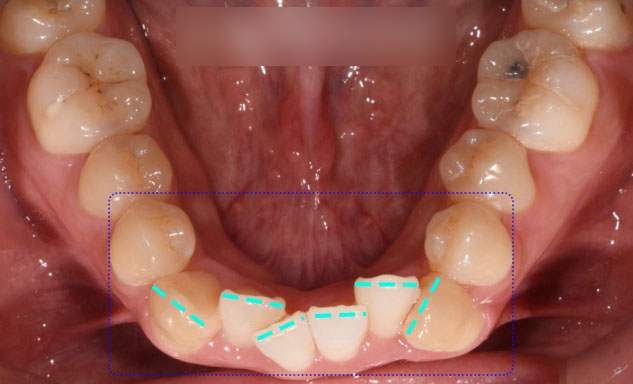

가지런하지 못한 앞니 치열도

눈에 띄었는데요.

이 부분은 총생으로

삐뚤빼뚤 정렬되지 못한 배열을 말하며,

특히 전치부에서 흔하게 나타납니다.

또한 이가 올바르게 맞물리지 않는

부분들에 대해서도

위치를 조정해 개선할 수 있습니다.

더불어 맞지 않았던 교합을 올리는 과정을 통해

점점 맞춰나갔습니다.

시작 후 12개월 후,

확실히 전과 달리 많이 바뀌어가고 있는데요.

가지런하지 못했던 배열은 물론이고

뻐드러져 보였던 덧니도

점점 제자리를 찾아가고 있습니다.